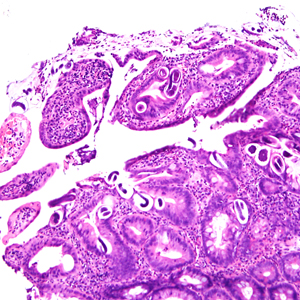

A 25-year-old male was hospitalized for Crohn’s exacerbation, duodenal outlet obstruction, and regional enteritis. He indicated that he has not had recent travel abroad. The patient underwent a gastroenterostomy and duodenal biopsy specimens revealed acute and chronic inflammation with crypt abscesses, focal ulceration, and reactive epithelial changes. Granulomata, epithelial dysplasia, and fibrosis were lacking. The attending pathologist also noted suspect parasitic organisms and the slides were sent to the state health department, which in turn forwarded them to the CDC-DPDx for diagnostic assistance. Figures A–F show what was observed on the slides received for testing. Figure A was taken at 100x magnification; Figures B–D at 400x magnification; and Figures E and F at 1000x magnification with oil. What is your diagnosis? Based on what criteria?

Figure A